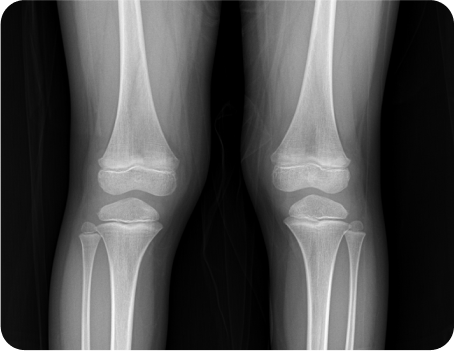

성장판 활성도 및 호르몬 검사 등의 기능적인 검사부터 체형과 측만증, 휜 다리 등의 구조적인 검사까지 놓치지 않으니까

성장판 활성화검사

평발/보행검사

성장추나

척추와 골반 무릎을 늘려주어 성장판 활성화,

틀어진 골반과 척추를 교정해 근육 긴장을 이완